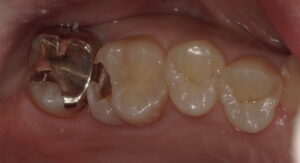

虫歯を全てとりきったところです。神経ギリギリまで進行していました(゜o゜)

レジン充填を行いました。